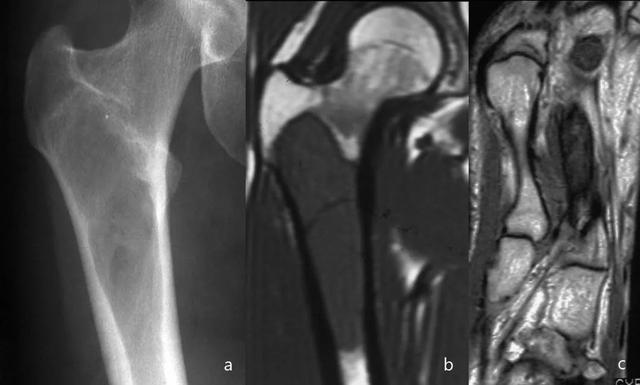

骨髓瘤的一个特征是具有“雨滴颅骨(raindrop skull)”的图案(图7和8)。

图7:骨盆X线片(a):跛行和右侧髋部疼痛的患者,右侧股骨近端明确的溶骨性病变(黄色箭头),皮质破坏。在CT研究(b,c,d和e)中,观察到多个明确边界的皮质下溶骨性病变(红色箭头),提示多发性骨髓瘤。通过骨活检确认诊断。